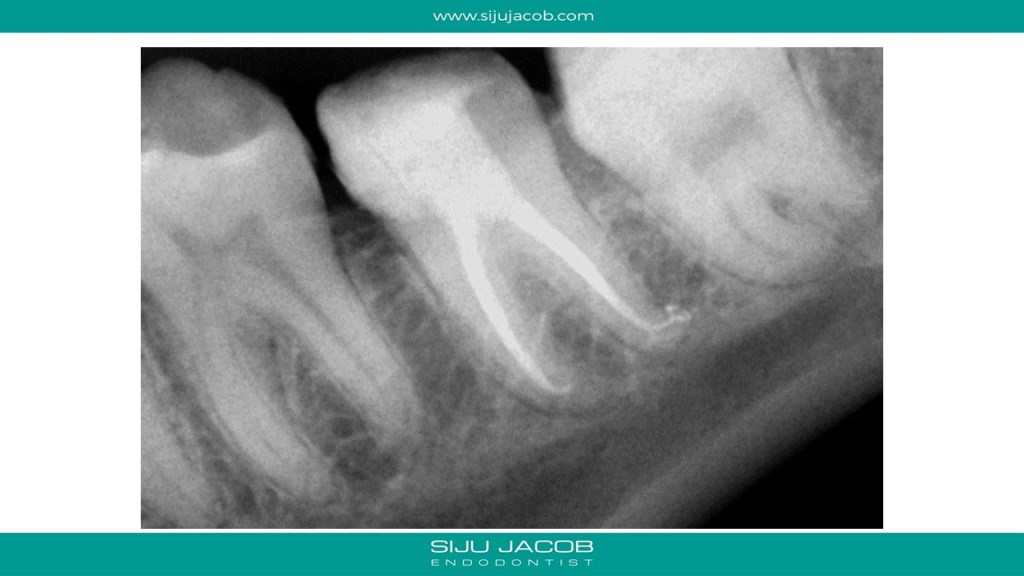

This was a bizarre case. Patient came from another state to Bangalore for a wedding. Came to the clinic with acute pain. She said that she had endo and crown done the previous week. She told me that the doctor who treated her used a microscope and also showed her pictures of three canals filled. I told her that on the radiograph, it looked liked her dentist had attempted to fill one canal. She was quite sure that she saw pictures of three canals filled. I removed the crown, reopened the access cavity and to my surprise found gutta percha mesially. It was in the periodontal ligament!